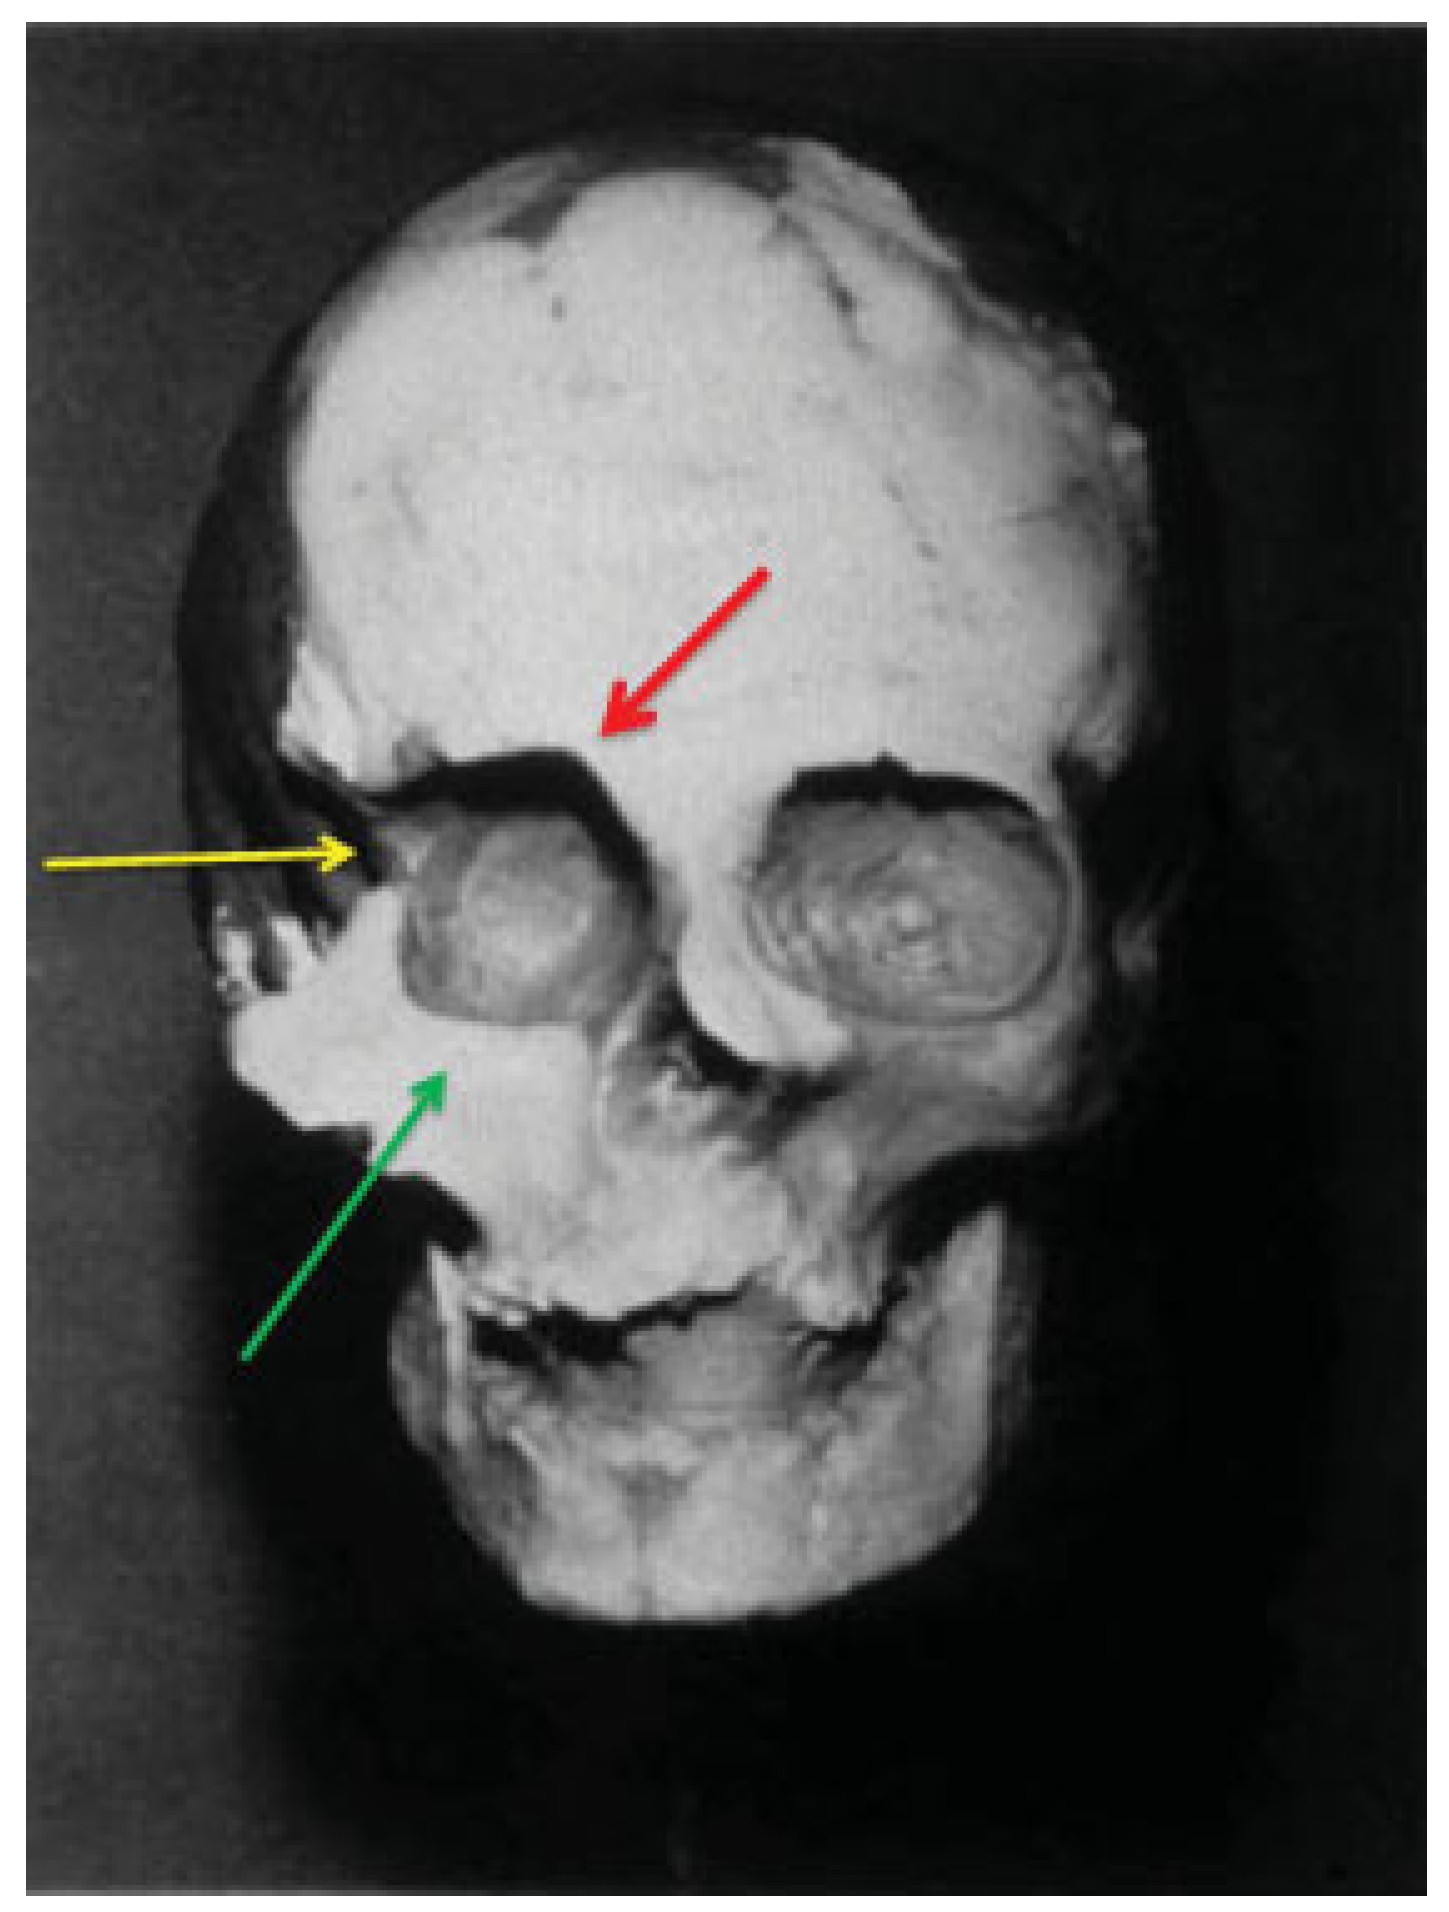

Did King Philip II of Ancient Macedonia Suffer a Zygomatico-Orbital Fracture? A Maxillofacial Surgeon's Approach

Results